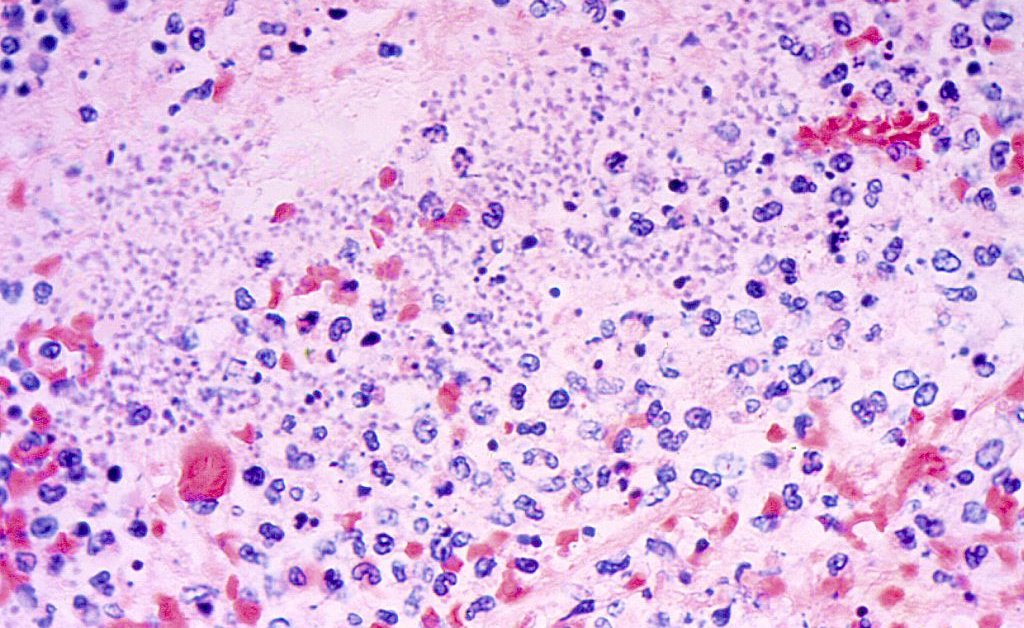

Pneumonic plague, which happens when the bacterium Yersinia pestis will get into an individual’s lungs, is each “the least frequent and most harmful sort of plague,” in response to the Cleveland Clinic.